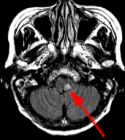

Fig. 1 Fig. 2 Fig. 3 Fig. 4

MRI Findings: In the supratentorial regions, some atrophy and chronic small vessel deep white matter ischemic changes were observed (Fig. 1) but no acute lesion or infarct was observed on MR diffusion. In the posterior fossa, however, a subtle small 1 cm hyperintensity can be seen in the left side of medulla on T2 weighted (Fig. 2) and FLAIR images (Fig. 3). This can be seen with an infarct, but its age would remain indeterminate. The MR diffusion image (Fig. 4) shows hyperintensity in the same region consistent with an acute infarct (arrows) as opposed to chronic ischemic changes.

Final Diagnosis: Based on the MR appearance, diagnosis of acute lateral medullary infarct was provided. This is a classic appearance of a posterior inferior cerebellar artery (PICA) infarct (PICA Syndrome), which may have thrombosed.